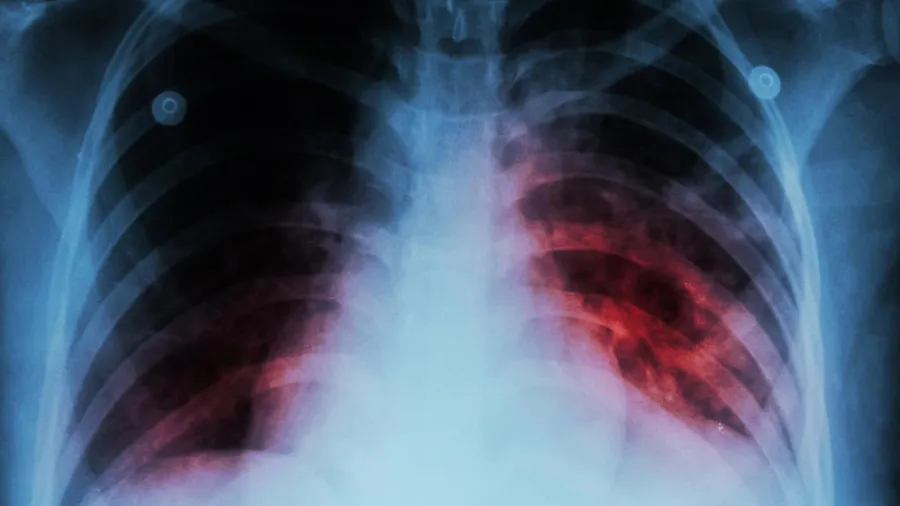

પાલ્મોનોલૉજિસ્ટ ડૉક્ટર લેંસલોટ પિન્ટોએ ચર્ચા દરમિયાન કહ્યું કે, લગભગ 40 ટકા લોકોમાં TBના લક્ષણ હોય છે. આ 40 ટકા લોકોમાં 5 ટકા લોકોને આ બીમારી પોતાના શિકાર બનાવી લે છે. તેમણે આગળ કહ્યું કે, TBને લઈને લોકો માનવા માગતા નથી કે તેઓ આ બીમારીની ઝપેટમાં છે. આ કારણે તેમની તપાસમાં મોડું થઈ જાય છે અને તેઓ TBના શિકાર થઈ જાય છે. જો તમને થોડા દિવસોથી ખાંસી હોય તો ડૉક્ટરને દેખાડવું જોઈએ.

જો ડૉક્ટરને દેખાડ્યા બાદ પણ ખાંસીની પરેશાની છે ડૉક્ટરની સલાહ પર TBની તપાસ કરાવવી જોઈએ. TBની તપાસની રીત પણ ખૂબ બદલાઈ ગઈ છે. પહેલા માઈક્રોસ્કોપથી જ્યારે તપાસ થતી તો તેમાં 40 ટકા TB ઉત્પન્ન કરનારા કિટાણુઓની જાણકારી મળી શકતી નહોતી, પરંતુ હવે નવી ટેક્નિકના માધ્યમથી થઈ રહેલી તપાસમાં ઘણું બધુ સ્પષ્ટ થઈ જાય છે. એ ખોટી ધારણાં બની ચૂકી છે કે TB માત્ર સમાજના ગરીબ વર્ગોથી આવનારા લોકોને જ ઝપેટમાં લે છે, જ્યારે એવું કશું જ નથી.

ડૉ. પિન્ટોએ આગળ કહ્યું કે, જો તમે ડાયાબિટિશના શિકાર છો તો તમને TB થવાનું જોખમ પણ વધારે છે. જો તમે સિગારેટ પીવ છો તો પણ તમને આ બીમારી ઝપેટમાં લઈ શકે છે. તેની સાથે જ જો તમને લીવર કે કિડની સાથે જોડાયેલી બીમારી છે તો પણ TBનો શિકાર સરળતાથી થઈ શકો છે. ચર્ચા દરમિયાન એક્સપર્ટ પેનલમાં સામેલ હેલ્થ સ્ટ્રેટેજિસના વરિષ્ઠ ડિરેક્ટર રમણ શંકરે પણ ઘણી મહત્ત્વની વાતો કહી.

તેમણે કહ્યું કે, ICMRના એક સર્વે મુજબ, TBના કેસોમાં લગભગ 64 ટકા લોકો એવા હોય છે, જેમનામાં લક્ષણ હોય છે, પરંતુ તેઓ તપાસ કરાવતા નથી. TBના લક્ષણોની સલાહ પર ઓળખ ન કરી શકવાથી આ બીમારીના દર્દીઓમાં વધારો થાય છે. પહેલાંની તુલનામાં આજના સમયમાં TBની તપાસના સારા વિકલ્પ ઉપલબ્ધ છે. કોરોનાની જેમ TBની ટ્રેસિંગ થવી જરૂરી છે. TB રોકવા માટે શહેર (મુંબઈ)માં BMC સ્વાસ્થ્યકર્મીઓએ ઘેર ઘેર જઈને TBની તપાસ કરવી જોઈએ. તો પેનલમાં સામેલ TB સર્વાઇવર મીરા યાદવે પોતાની કષ્ટોથી ભરપૂર ટ્રીટમેન્ટ જર્ની બાબતે જણાવ્યું. તેણે કહ્યું કે, વર્ષ 2013માં તેને ખબર પડી કે TB થઈ છે. તેની TBની જર્ની ખૂબ જ મુશ્કેલ હતી.

TBની અસર માત્ર દર્દી જ નહીં, પરંતુ તેની સાથે જોડાયેલા લોકો પર પણ પડે છે. તેને આ ખતરનાક બીમારીથી બહાર નીકળવામાં લગભગ 4 વર્ષનો સમય લાગી ગયો. તેને આ બીમારીના કારણે ફેફસા પણ ગુમાવવા પડ્યા. જો કોઈને TB જેવી ગંભીર બીમારી થાય છે તો તેની સમય પર સારવાર ખૂબ જરૂરી છે. જો ઓળખમાં મોડું થાય છે તો TBની બીમારી ઘણી હદ સુધી બગડી જાય છે. તેના ઘણા સ્ટેજ હોય છે. થોડી ગંભીર કન્ડિશનમાં દવાઓની અસર પણ ઓછી થઈ જાય છે અને TB ગંભીર રૂપ લઈ લે છે તો દર્દીનું બચવું મુશ્કેલ થઈ જાય છે.